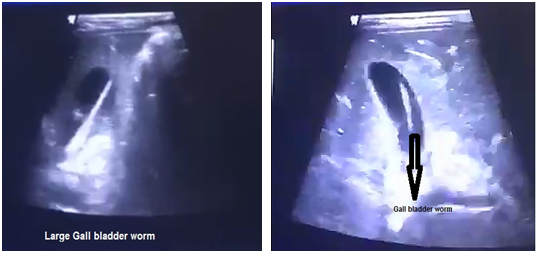

In 20 cases with biliary ascariasis observed with ultrasonography, there were 8 patients with gallbladder (Figure 1-2) and 7 with worms in the common bile duct (Figure 3-4). In 5 cases, the worms were found in the main hepatic duct (Figure 5-6) and pancreatic duct (Figure 7-8) and no case was seen with complicated intrahepatic abscess cavity. Ultrasound confirmed the dilatation in common bile duct as estimated about 10-20 mm, in 7 patients (Table 1 and Pie chart 1).

Figures 1-2 Gall bladder worm.